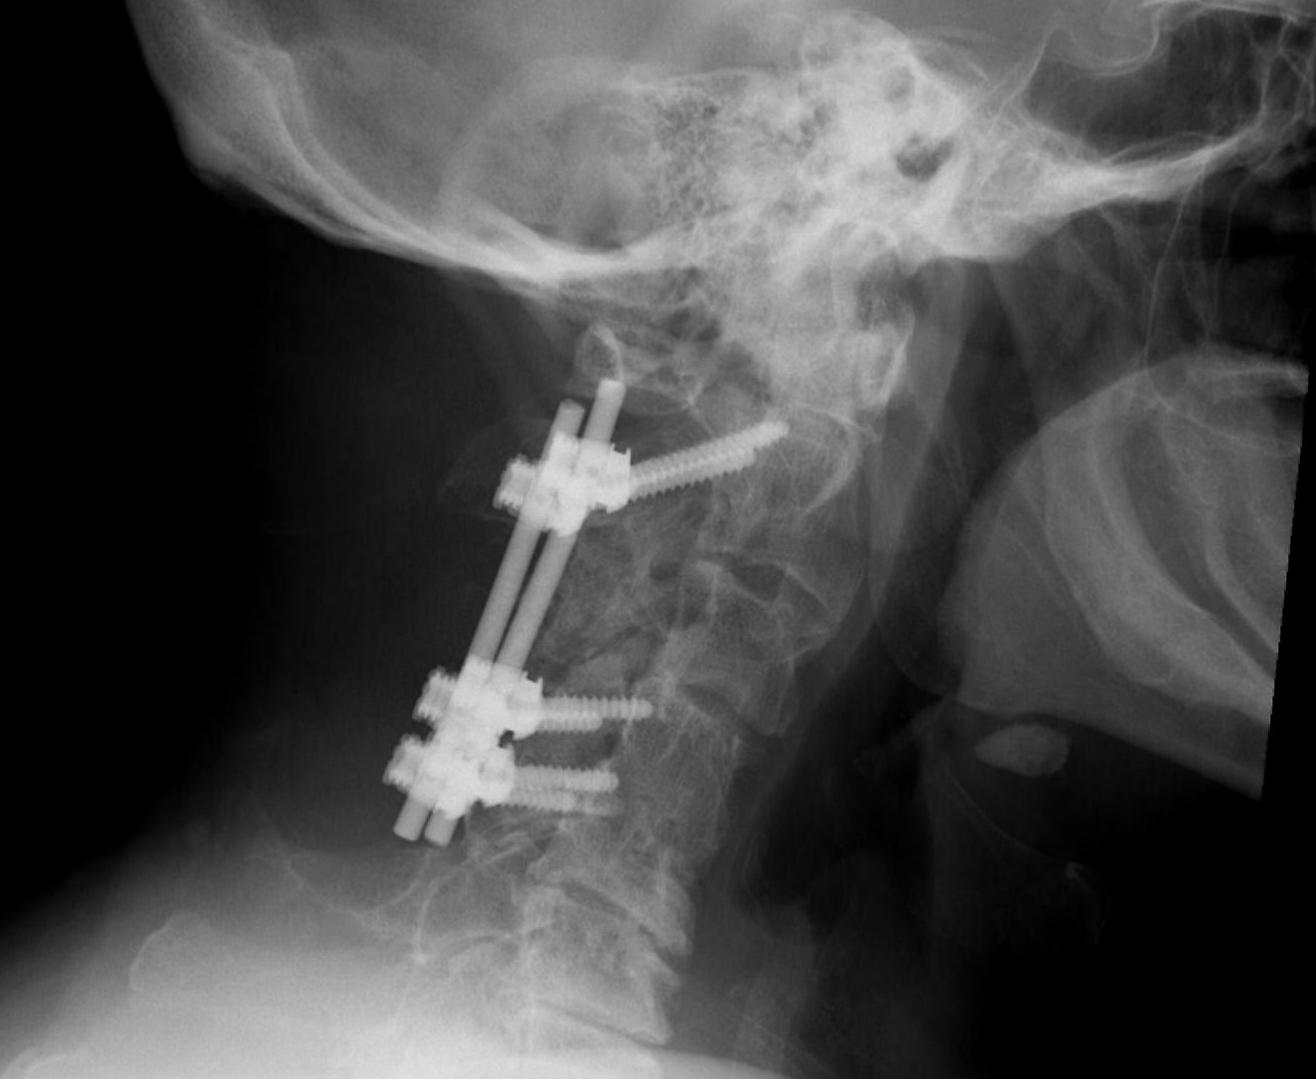

Operative Management

Indications

Significant displacement / angulation with disc and PLL damage

- Type II

- Type IIa

- Type III

Options

Anterior fixation / fusion

Posterior fixation / fusion

Combined

Posterior

1. Posterior C1 - C3 fusion

2. C2 trans-pedicle screw fixation + C3 fixation +/- fusion

Short segment fixation +/- fusion